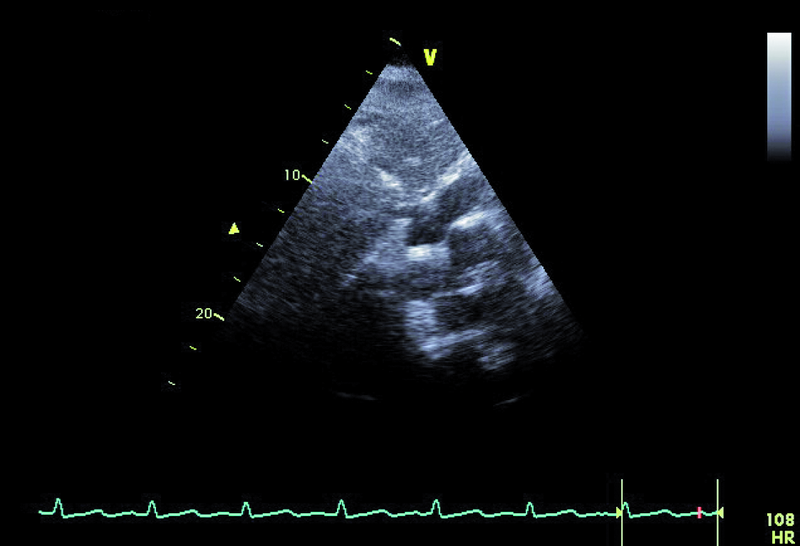

Powodem hospitalizacji 74-letniej kobiety był wielogodzinny ból w klatce piersiowej z towarzyszącą dusznością i niskim ciśnieniem tętniczym (90/60 mm Hg). W dniu hospitalizacji wystąpiło także krótkotrwałe omdlenie. W EKG zwracały uwagę cechy przebytego zawału serca ściany dolnej oraz brak progresji załamka R w odprowadzeniach V1-V4. Pacjentka od kilku lat chorowała na cukrzycę i nadciśnienie tętnicze. Po krótkotrwałym pobycie na oddziale szpitala rejonowego chorą przeniesiono do ośrodka referencyjnego. W wykonanej w trybie pilnym koronarografii uwidoczniono nieistotne zmiany miażdżycowe w naczyniach wieńcowych – maksymalnie do 40%. Wywiad, dziesięciokrotnie podwyższone stężenie d-dimeru i troponiny oraz powiększenie jamy prawej komory w badaniu echokardiograficznym stanowiły podstawę do poszukiwania zatorowości płucnej. Wykonane badanie TK klatki piersiowej pozwoliło uwidocznić skrzeplinę obejmującą pień oraz gałęzie płucne do poziomu tętnic segmentalnych. Ze względu na brak poprawy klinicznej w trakcie podawania heparyny zastosowano leczenie fibrynolityczne (alteplaza). Z powodu gorączki zastosowano także antybiotyk. W USG jamy brzusznej nie stwierdzono procesu nowotworowego, a badanie układu żylnego kończyn dolnych uwidoczniło skrzeplinę w żyle podkolanowej. Po kilku dniach od podania leku fibrynolitycznego obserwowano stopniowe ustępowanie duszności, stabilizację ciśnienia tętniczego, zmniejszenie parametrów zapalnych i stężenia d-dimeru. Rejestrowano także wzrost ciśnienia parcjalnego tlenu we krwi obwodowej. Dziesięć dni później wykonano kontrolne badanie echokardiograficzne (ryciny).

Dowodem klinicznym masywnej zatorowości płucnej był u chorej epizod omdlenia, utrzymująca się duszność, niskie ciśnienie tętnicze. Wiodącą rolę w rozpoznaniu choroby pełni tomografia komputerowa. Badanie echokardiograficzne uznawane jest za uzupełniające. Powiększenie jamy prawej komory stwierdzane w dniu hospitalizacji mówiło o możliwości istotnej dysfunkcji łożyska płucnego. Masywna zatorowość jest wskazaniem do włączenia leczenia fibrynolitycznego, zmniejszającego śmiertelność i zapobiegającego nawrotom choroby. Stan kliniczny pacjentki w wyniku zastosowanej alteplazy poprawił się. Rejestrowano zmniejszenie stężenia d-dimeru i troponiny. Czy jednak sytuacja chorej nie budzi już niepokoju? Mimo ograniczonej jakości przedstawionych rycin można dostrzec, że jama prawej komory jest przeciążona (ryc. 1, 2), a ciśnienie w łożysku tętnic płucnych szacowane z czasu akceleracji wypływu (66 ms!) jest podwyższone (ryc. 3). Im większa jest obstrukcja łożyska płucnego, tym więcej cech dysfunkcji prawej komory stwierdza się w badaniu ultradźwiękowym. Warunki obrazowania utrudniały odniesienie się do odcinkowej kurczliwości ściany wolnej i potwierdzenie lub wykluczenie objawu McConnella, czyli dysfunkcji segmentu środkowego. Ze względu na trudność w wizualizacji wsierdzia nie można było także ocenić zmiany pola powierzchni prawej komory (RV FAC). Mimo zachowanej funkcji kurczliwej prawej komory mierzonej wartością przemieszczenia pierścienia trójdzielnego (ryc. 4) uważny czytelnik z pewnością dostrzeże tkwiącą w prawej tętnicy płucnej skrzeplinę (ryc. 5, 6). Rzadko udaje się bezpośrednio uwidocznić skrzeplinę w łożysku tętnic płucnych. Kontrolne badanie TK klatki piersiowej potwierdziło obecność tzw. zatoru jeźdźca w pniu płucnym ze skrzeplinami w gałęzi prawej i gałęziach segmentalnych do płata dolnego prawego płuca. Obserwowano jedynie częściową regresję skrzeplin z tętnic płatowych i segmentalnych. Mamy więc do czynienia z nieskutecznością leczenia fibrynolitycznego (no clot resolution). Dobry stan kliniczny chorej nie wskazywał na potrzebę zastosowania leczenia chirurgicznego i embolektomii. Nie podjęto także decyzji o powtórnym leczeniu fibrynolitycznym z użyciem innego środka. Postanowiono kontynuować leczenie przeciwkrzepliwe i przeprowadzić po kilku tygodniach ponowną ocenę stanu klinicznego pacjentki i stanu łożyska tętnic płucnych. Wobec wieku chorej i licznych obciążeń internistycznych interesującą opcją leczenia (ale niestosowaną w tutejszym ośrodku) byłaby trombektomia za pomocą cewnika z miejscowym podaniem leczenia fibrynolitycznego.